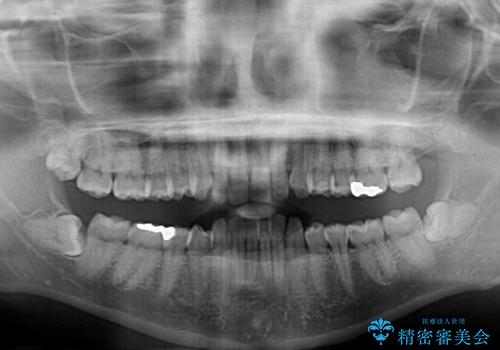

- 下顎前歯部には叢生が認められ、口を自然に閉じにくい状態でした。また、噛み合わせが深い「ディープバイト」の状態で、見た目だけでなく将来的な奥歯への負担も懸念されました。

口元の突出感を改善するため、上下左右の小臼歯4本を抜歯する矯正治療を計画しました。